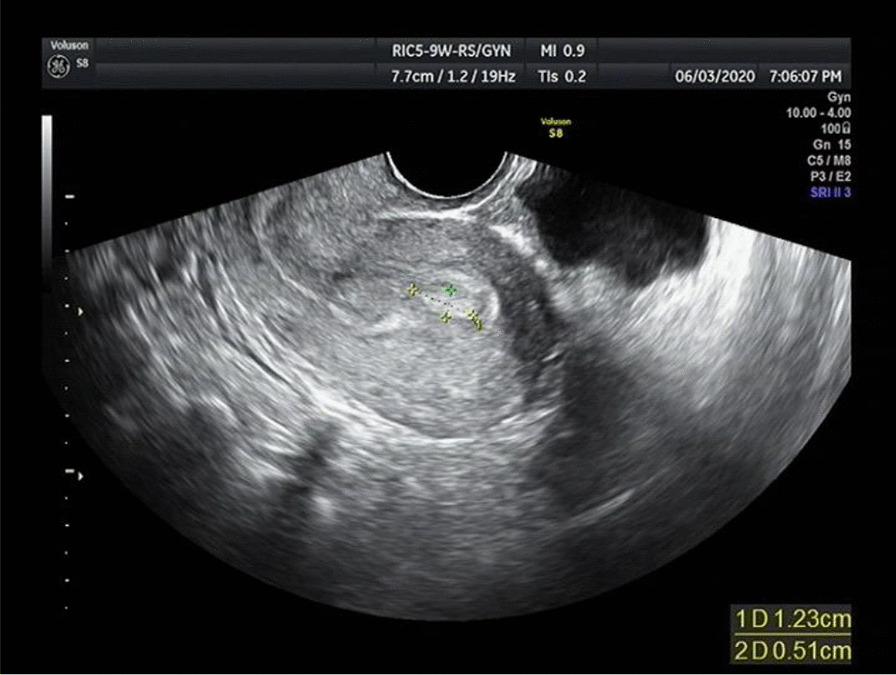

The drug treatment for 23 patients with APA-L was as follows: 8 were treated with high-performance progestogen, 6 were given medroxyprogesterone or progesterone in the second half of the menstrual cycle, 4 were on short-acting oral contraceptives, and 5 were followed up regularly without medication. Hysteroscopy and endometrial biopsy were performed every 3 to 6 months to evaluate the histological changes in the endometrium. If the endometrium was normal with two consecutive endometrial biopsies, then regular hysteroscopy and endometrial biopsy were no longer needed. In addition, menstruation and transvaginal ultrasound were performed to look for abnormal growth of the endometrium showing the characteristic B-ultrasound appearance of APA (Fig. 3).

Fig. 3.

Atypical polypoid adenomyoma on B-ultrasound (endometrium 1.0 cm, intrauterine hyperechoic mass 1.7*1.2 cm)